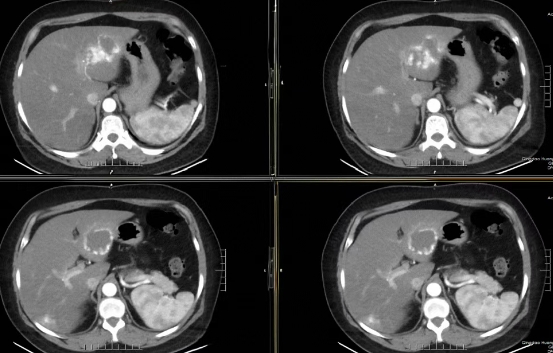

术前增强CT示肝内多发血管瘤

术后复查CT,瘤体内碘油沉积良好